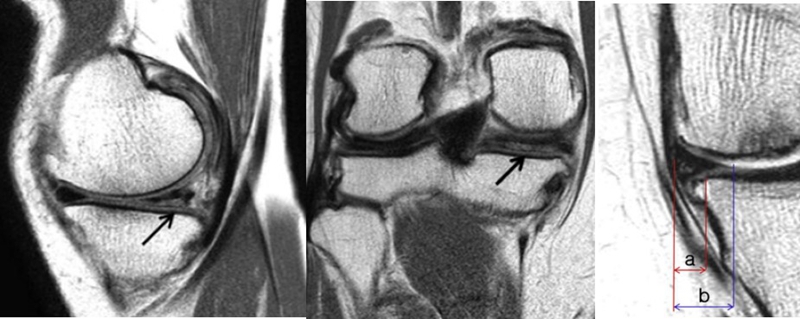

早期(3月内)内侧半月板相对挤压百分比≥33%,是SONK发病1年后预后不良的预测指标,MRI检查没有局灶性轮廓塌陷和髁深处没有低信号线(隔离带),预后好,股胫角>180°(下肢力线内翻>6°)和MRI上深度>20mm 预示SONK患者症状发作后1年预后不良。

内侧半月板挤压(MME)以绝对值和挤压相对百分比 (RPE) 的形式呈现,其定义为挤压半月板宽度与整个半月板宽度相比的百分比